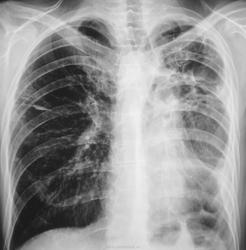

Прошел год, пациент значительно потерял в весе, температура около 38 градусов, кашель с мокротой и был доставлен в рентгеновский кабинет на носилках.

"Ой"! Воскликнули фтизиатры, это наше! На носилках пациент был срочно госпитализирован в областную туб больницу в тяжелом состоянии. Лечение, со слов фтизиатров, было не легким, так сказать - "на грани", пациент был прооперирован.